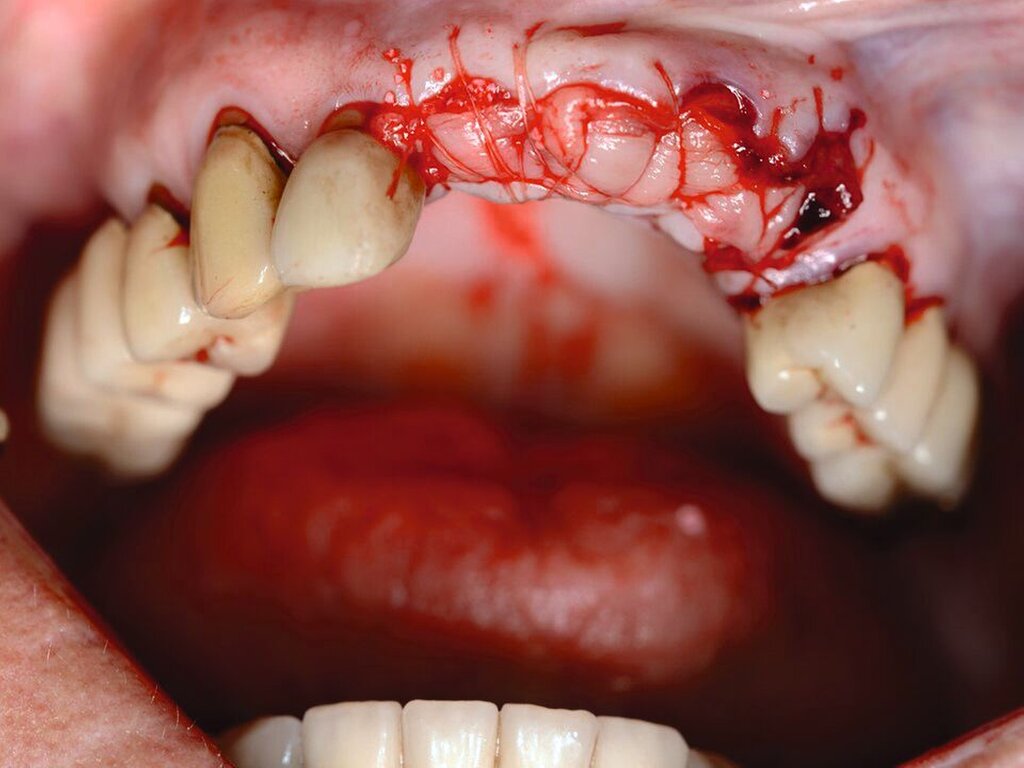

Eine Dekoronation ist eine chirurgische Intervention, die durchgeführt werden kann, wenn aufgrund ausgeprägter Schädigungen der desmodontalen Zellen und der Wurzeloberfläche eine Resorption auftritt. Im Rahmen der klinischen Untersuchung imponiert der betroffene Zahn aufgrund der Ankylose mit einem metallischen (hellen) Klopfschall. Röntgenologisch lassen sich Resorptionslakunen an der Wurzeloberfläche erkennen. Bei progressiver Resorption und Infraposition des betroffenen Zahnes in Relation zur Restdentition kann eine Dekoronation indiziert sein [Malmgren et al., 2015] (Abbildung 2).

Das Ziel der Dekoronation ist es, die klinische Krone unter Belassung der resorbierenden Wurzel zu entfernen, damit der Alveolarknochen aufgrund der Knochenneubildung bei Ersatzresorption erhalten und eine optimale Voraussetzung für spätere Interventionen gegeben werden kann [Malmgren et al., 2006]. Bei Patienten im Wachstum kann die Dekoronation eine sinnvolle Therapieoption darstellen, um den teils erheblichen Knochenverlust in Verbindung mit der chirurgischen Entfernung der ankylosierten Zahnwurzel zu vermeiden (Empfehlung 60).